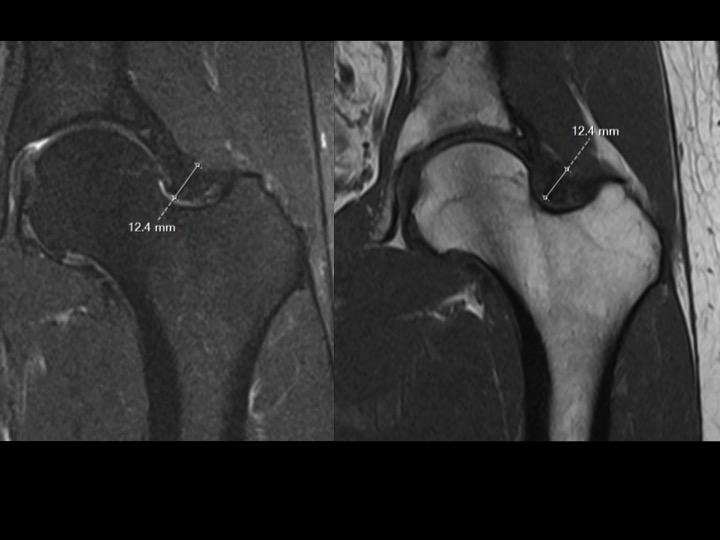

42M chronic pain with reported work injury 17 months ago

There is marked dark signal capsular thickening anteriorly and superiorly (white arrows). The reference, based on arthrography, refers to much thinner capsular measurements, and does not specify where measurements are made (these are mid superior and anterior). Is this chronic adhesive capsulitis? There is also insertional G Minimus tendinosis (yellow arrows) and degenerative tearing of the anterior labrum. The patient specified that pain is worst posteriorly. Last image from a different patient today with comparatively normal appearing capsule. Reference article.